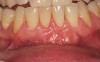

Fig 1. Miller Class I recession on tooth No. 11 (Fig 1) treated with tuberosity CTG (Fig 2). Note this CTG (which is the tuberosity CTG from Fig 5) was placed before the practitioner developed thinning techniques, so a keloid-like appearance was observed even 1 year after grafting.

Figure 1

Fig 2. Miller Class I recession on tooth No. 11 (Fig 1) treated with tuberosity CTG (Fig 2). Note this CTG (which is the tuberosity CTG from Fig 5) was placed before the practitioner developed thinning techniques, so a keloid-like appearance was observed even 1 year after grafting.

Figure 2

A complication in using CT from the tuberosity reported in the literature is a tendency for clinicians to harvest tissue that is too thick.12 This can result in a keloid-like appearance similar to what may occur with an EPG. This excess thickness can be unesthetic (Figure 1 and Figure 2) and subsequently require a gingivoplasty to remove the superfluous tissue.12 This problem may perhaps be alleviated with proper thinning of the graft prior to insertion into the recipient area.